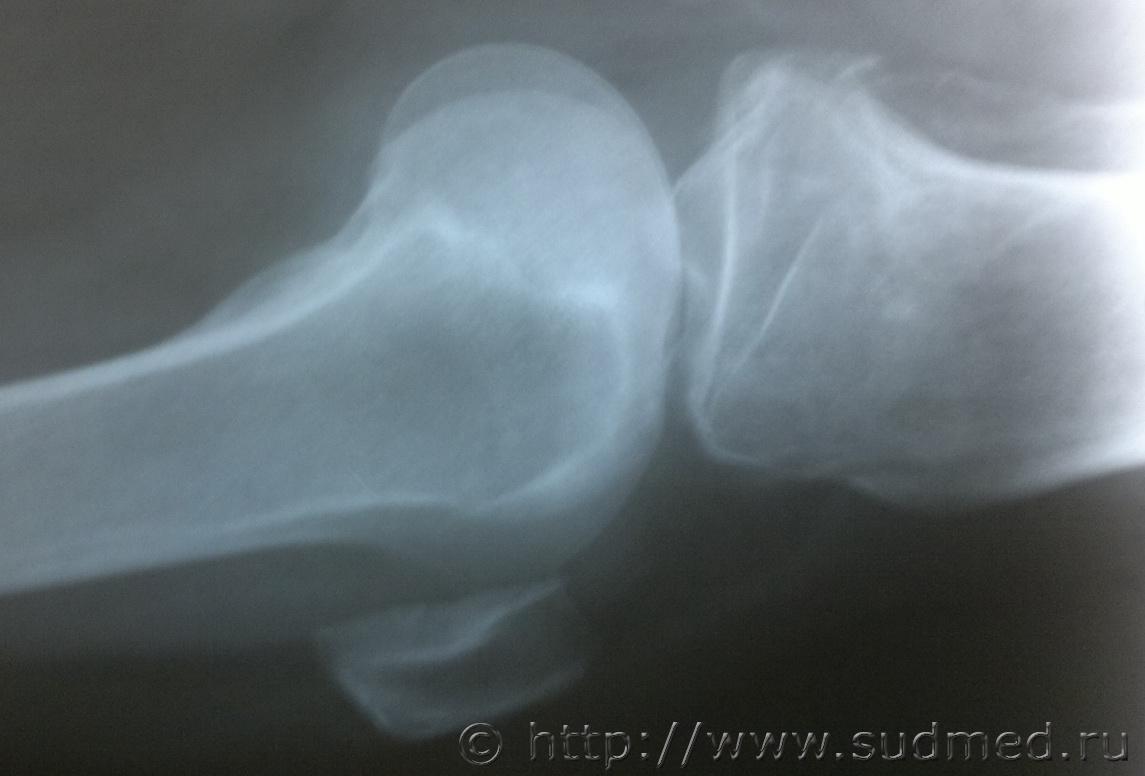

Женщину, 70 лет сбил автомобиль, после чего она была доставлена в ОКБ где были сделаны рентгеновские снимки, которые прилагаю, достаточно ли будет снимков для определения степени вреда здоровью, так как точный диагноз из истории болезни не удалось узнать.Судебная медицина - Прикрепленное изображение Судебная медицина - Прикрепленное изображениеСудебная медицина - Прикрепленное изображениеСудебная медицина - Прикрепленное изображениеСудебная медицина - Прикрепленное изображение

достаточно. Единственное, что по снимку непонятно - открытый или закрытый перелом? В украине это имеет существенное значение для определения степени тяжести, если Вы из России - коллеги точнее скажут, но судя по локализации здесб вроде будут тяжкие телесные

тяжкий вред.

Большое спасибо за быстрый ответ, закрытый перелом обеих ног.